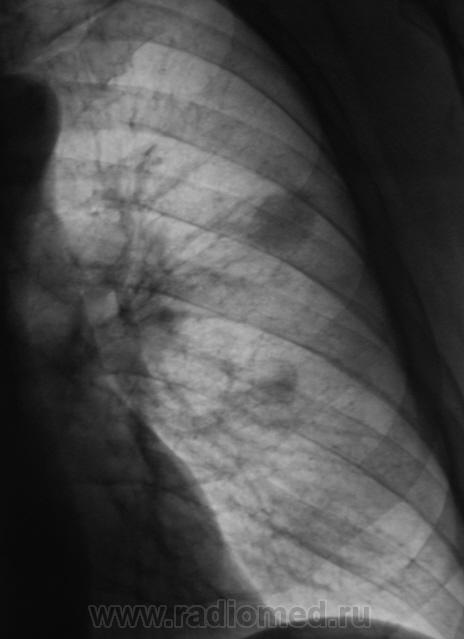

Пациент "взят на контроль" при расшифровке цифровых флюорограмм, дообследован - рентгенография в стандартных проекциях. Ваше мнение коллеги?

Произведены томограммы.